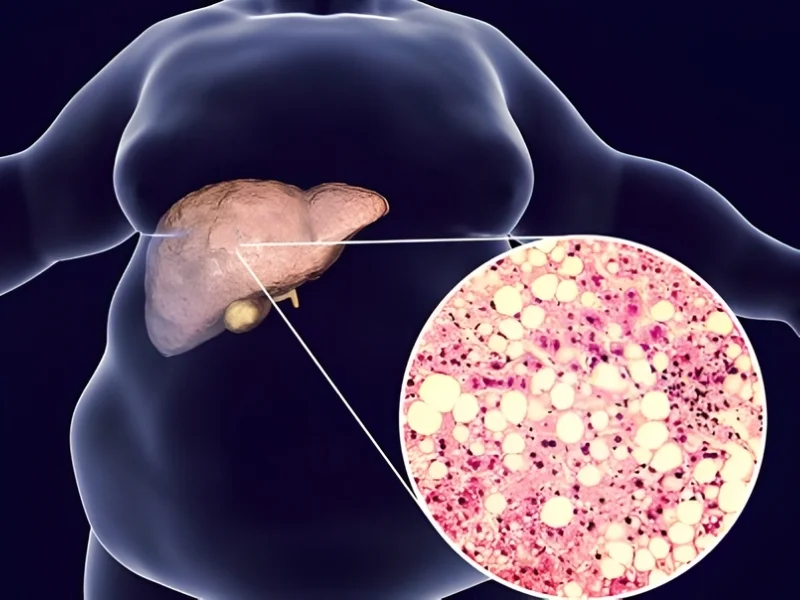

Chronic liver disease or cirrhosis

Excessive Alcohol Consumption